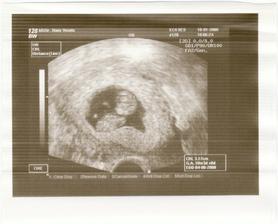

10+3...krásně rosteme a držíme se